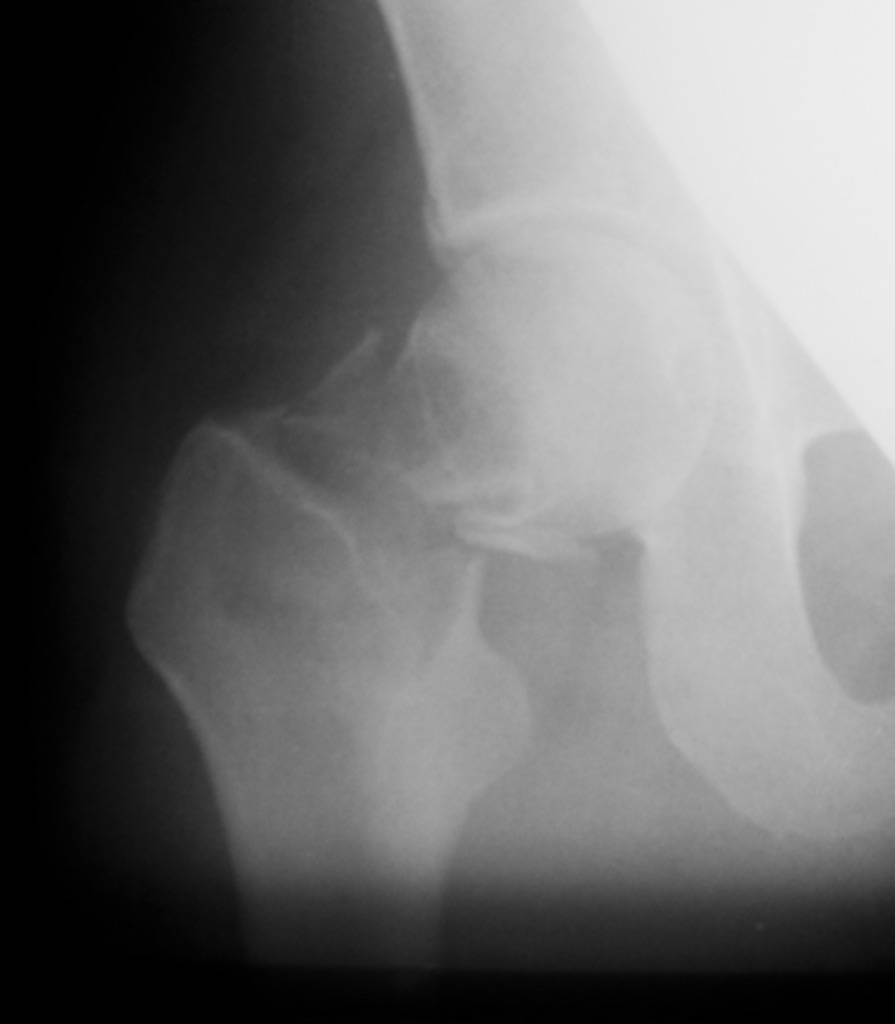

Re: Патологический перелом шейки + беременность

"Поправил" рентгенограмму. Так не лучше?